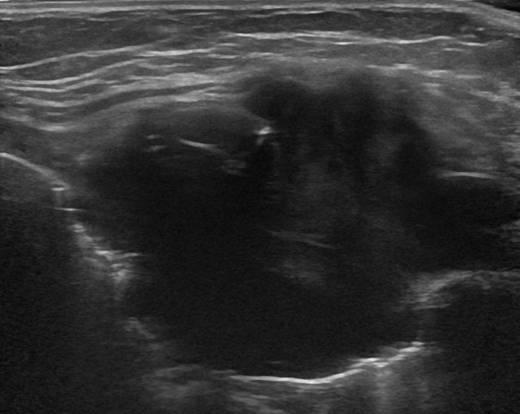

Di căn thành ngực - Ảnh 3

Di căn thành ngực

» Thông tin: Nam giới – 64 tuổi.

» Lâm sàng: Khối thành ngực / K vòm.